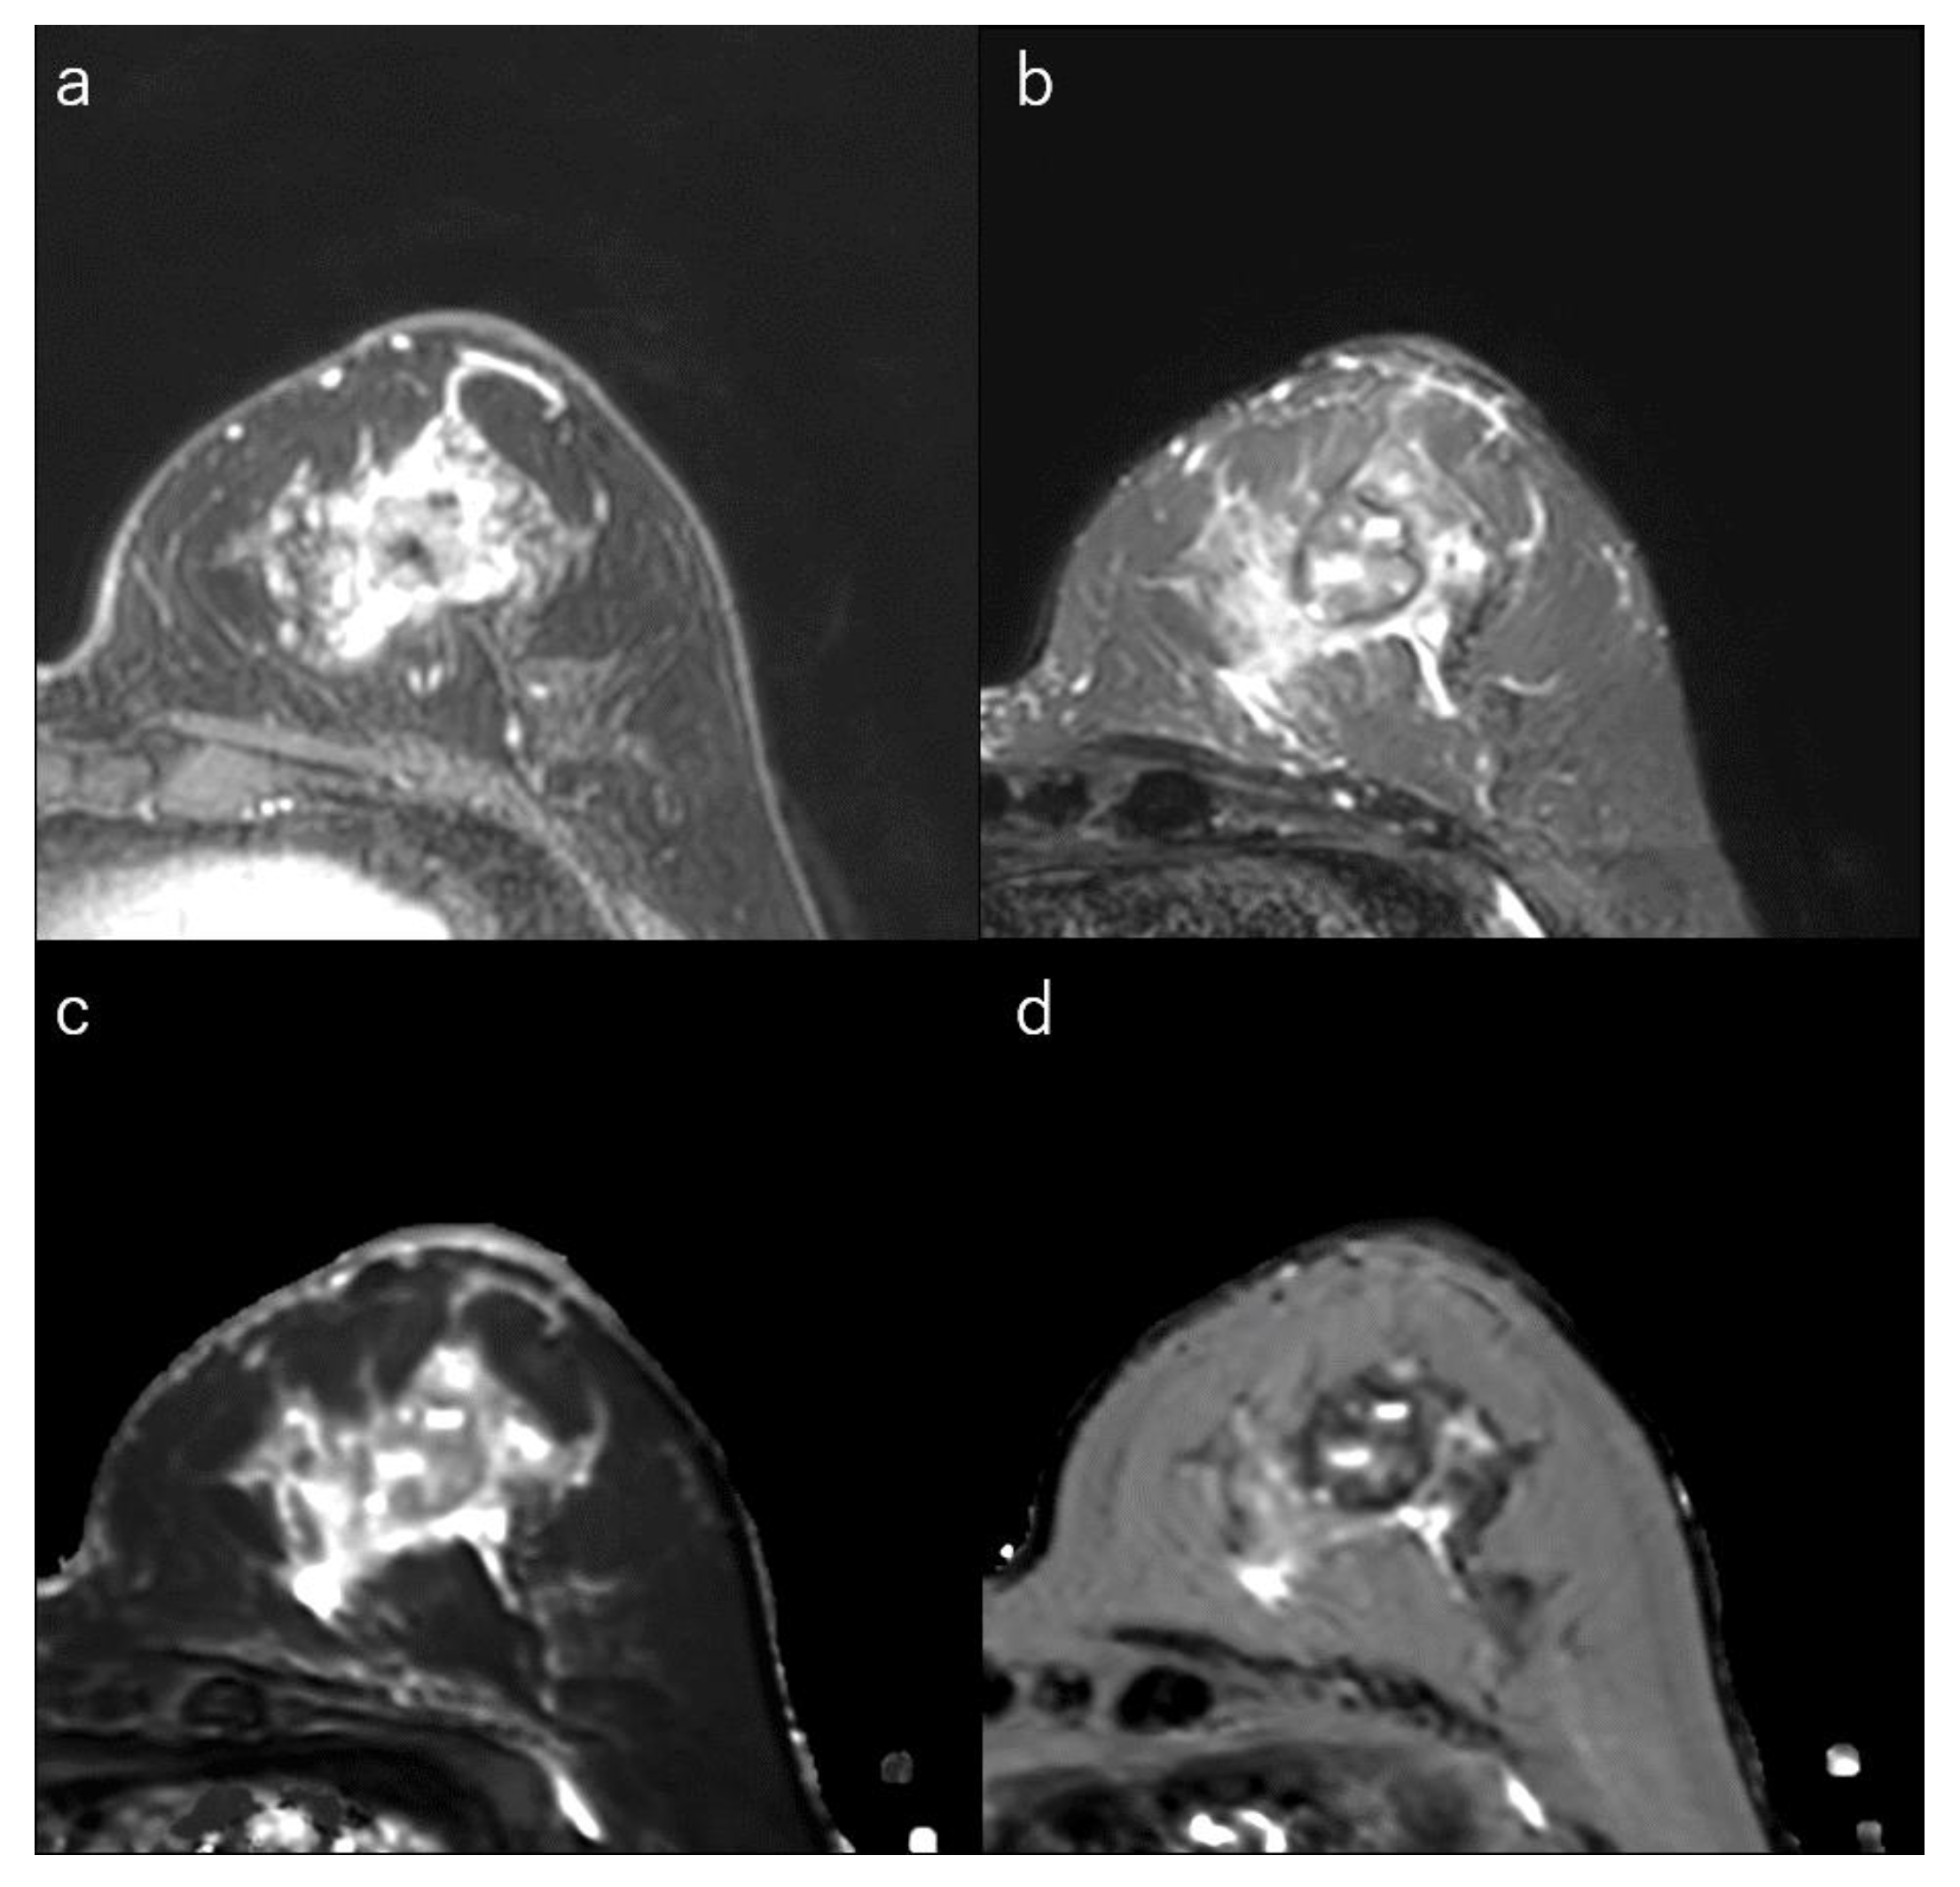

Figure 6.

(a) Dynamic contrast-enhanced MR image in a 73-year-old woman with triple-negative breast cancer shows an irregular mass with rim enhancement. (b) Short-tau inversion recovery image shows focal areas of very high signal within the mass. (c) T1 map (window width/centre = 1400/2400 ms) shows focal very high signals; Mean T1 of the mass is 1533 ms. (d) T2 map (window width/centre = 160/240 ms) shows focal very high signals within the mass; and mean T2 of the mass is 113 ms.

TN breast cancer is highly associated with the presence of a central scar, tumour necrosis, the presence of spindle cells or squamous metaplasia, high total mitotic count, and high nuclear-cytoplasmic ratio [9,10,145]. These cancers are also more likely to show round, oval, or lobulated masses and are more likely to be unifocal compared to ER+/PR+/HER2 tumours [29,145,146,161,162]. MRI often shows areas of intratumoral high T2 signal intensity, lobulated shape, rim enhancement, and smooth margins (Figure 6) [29,144,145,146,162]. The rim enhancement can be explained by high angiogenesis in the periphery of the tumour. Very high intratumoral signal intensity on T2-weighted MR images and an elongated T2 relaxation time may be associated with intratumoral necrosis [29,123,145]. When the necrotic areas are included, the ADCs of TN cancers are higher than of luminal-type breast cancers [29,51,78,96].